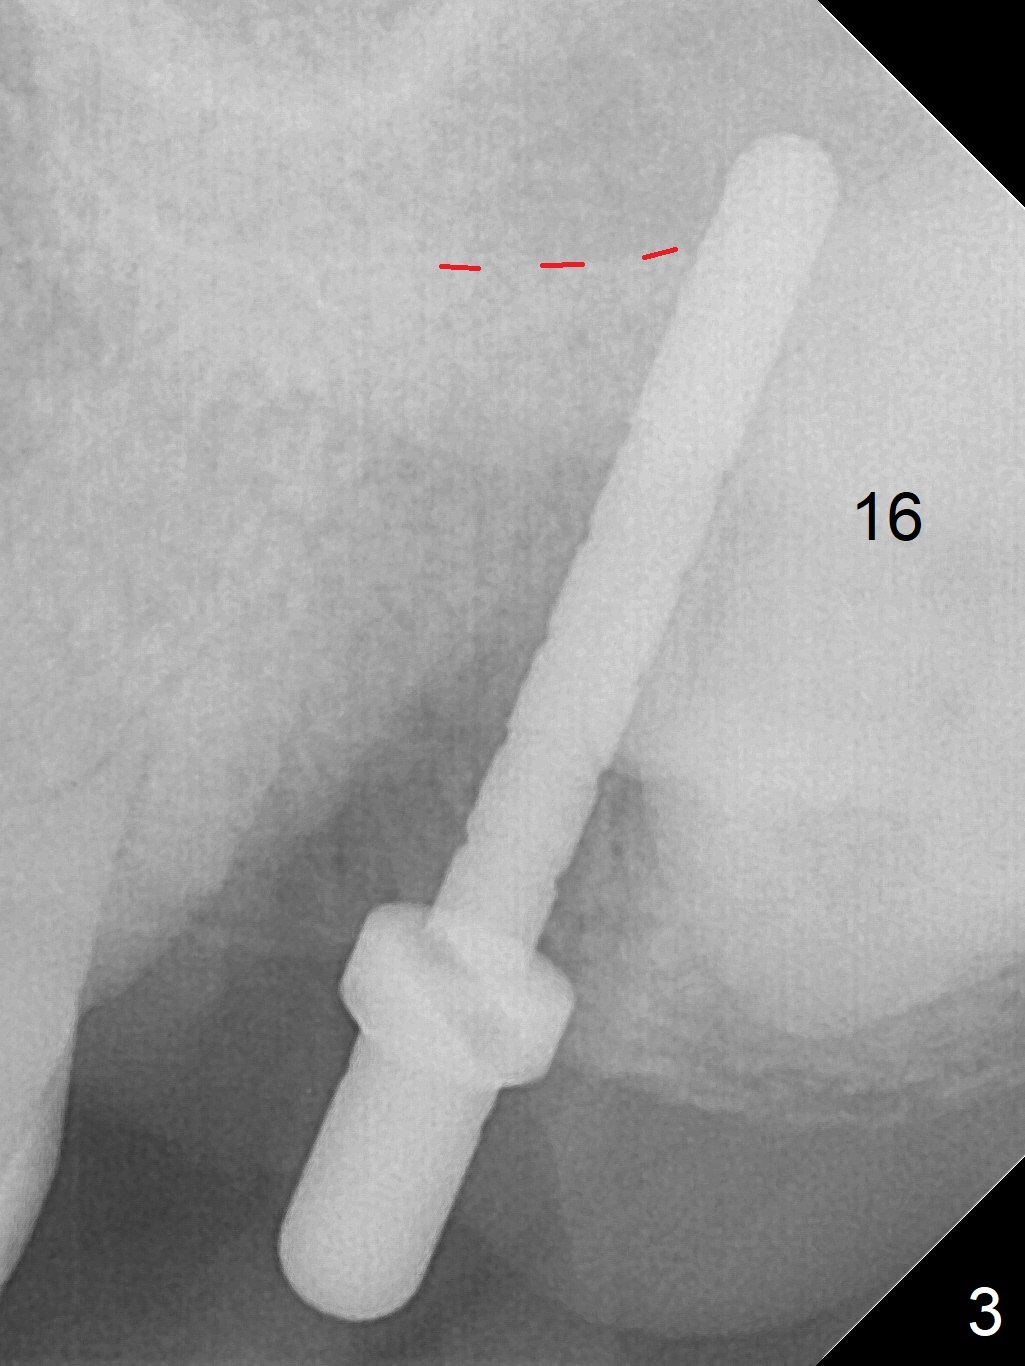

Extraction of the tooth #15 with short clinical crown (suggesting bruxism, Fig.1) reveals a vertical root fracture (Fig.2 <). It seems unnecessary and difficult to create osteotomy in the mesial slope. What can be done is to place starter and 2 mm drills as mesial as possible (Fig.3 (red dashed line: sinus floor). After use of Lindamann bur to move the osteotomy mesially and sequential osteotomy until 3.8x18 mm, a 4.5 mm tap is inserted with clearance from the impacted tooth #16 (Fig.4). A 5x15 mm implant is placed with >60 Ncm with clearance from the 3rd molar (Fig.5,6). If the impacted tooth were removed, the primary stability is expected to be reduced. Impression is taken 6 months postop with 19/20 implants (Fig.7). The bone graft remains in the crestal area immediately and 11 months post cementation (Fig.8,9 *). In the other word, new crestal bone forms after extraction.